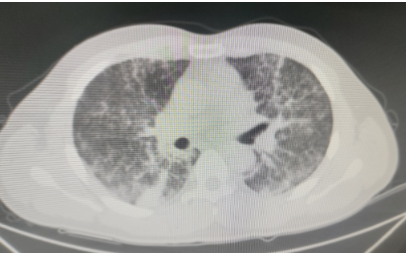

龙先生,36岁,在浙江务工,与朋友一行数人到树林捕捉竹鼠。回老家花垣县后即出现了发热、咳嗽、乏力等症状,他一开始没有特别在意。几天过去了,症状一点也没有缓解,并出现了胸闷、气短,便来到花垣县人民医院就诊。医生为他安排胸部CT检查,结果显示,他的双肺出现了弥漫分布斑片状增高影,边缘模糊。结合患者临床症状、胸部影像学和流行病学史,医生高度怀疑他很可能是感染了特殊病原体,于是为他进行了支气管镜检查,留取肺泡灌洗液送检病原体靶向测序。检测结果出来,确诊为马尔尼菲篮状菌感染,其序列数高达10190,医生立即为龙先生进行抗真菌、对症一系列治疗,肺部炎症逐渐吸收,阴影缩小。

龙先生肺部影像呈现弥漫分布斑片状增高影